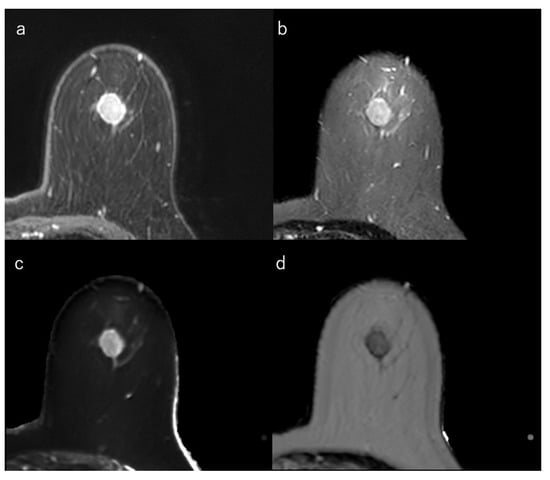

Figure 3.

(a) Dynamic contrast-enhanced MR image in a 50-year-old woman with luminal-A type breast cancer shows a spiculated mass. (b) Short-tau inversion recovery image shows a low signal mass. (c) T1 map (window width/centre = 1400/2400 ms) shows an intermediate signal mass; Mean T1 of the mass is 986 ms. (d) T2 map (window width/centre = 160/240 ms) shows a low signal mass; mean T2 of the mass is 62 ms.

This section explains the MRI characteristics of the breast cancer subtypes. In general, HR-positive tumours demonstrated stromal reaction, fibrosis, and perilesional spiculations [139]. An irregular mass margin and a non-round shape were significantly associated with luminal-A-type cancers [32,140,154]. Intratumoral iso/low T2-signal intensity may reflect fibrosis and is also associated with the luminal subtypes [14,140,141,142]. Multifocal or multicentric carcinoma is less common in the luminal-A type than in the luminal-B or HER2 types [140,155]. Compared to the other subtypes, luminal-A-type breast cancers tended to show less strong enhancement [35]. Kato et al. reported that rim enhancement occurred significantly less frequently in luminal-A-type breast cancers [85] (Figure 3).